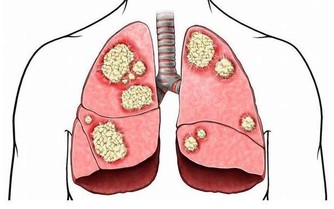

愛喝啤酒如果已經患了腎臟方面的疾病,又經常大量喝啤酒,

會使尿酸沉積導致腎小管阻塞,造成腎臟衰竭。